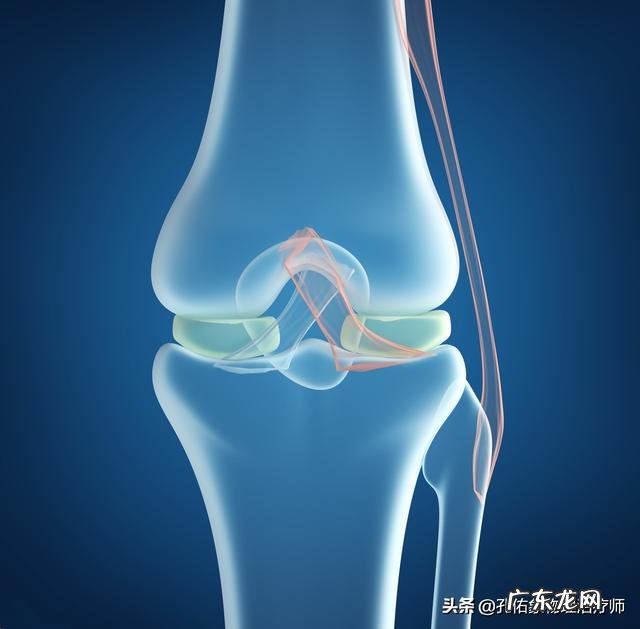

一般根据上面描述的情况,看您自己的半月板是怎么损伤的,是损伤在哪个部位?比如说是红区的损伤,若是症状较轻,肿胀不明显,只需要在损伤的急性期注意少让膝关节有过多的负荷活动,比如上下楼、下蹲等,一般的正常行走还是基本可以进行的,这样也可以自行愈合 。若是红区损伤后,症状严重,以及红白区的损伤还是建议根据MRI结合,及早行关节镜下,半月板的修复术,术后一般是需要相对制动4-6周的,不要有过多的行走,负重,尽量使用辅助手杖减轻膝关节的负荷,同时加强膝关节的康复锻炼 。若是白区的损伤,即使手术修复后,也很难愈合,可能会考虑摘除半月板 。